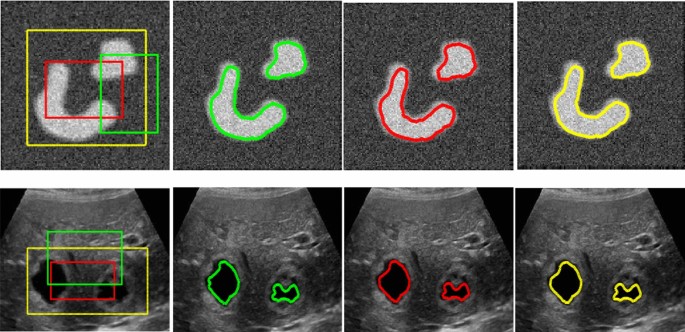

Pengolahan citra medis telah menjadi bidang yang semakin penting dalam dunia kedokteran modern. Salah satu teknik yang digunakan dalam pengolahan citra medis adalah segmentasi, yaitu proses pemisahan objek atau struktur yang ingin diidentifikasi dari latar belakang citra. Dalam kasus citra kepala MRI (Magnetic Resonance Imaging), segmentasi dapat membantu dokter dalam mendiagnosis dan memahami kondisi pasien dengan lebih baik. Salah satu metode yang digunakan dalam segmentasi citra kepala MRI adalah metode Active Contour.

Citra kepala MRI menyediakan informasi rinci tentang struktur otak, jaringan lunak, dan abnormalitas potensial lainnya dalam area kepala. Namun, citra-citra ini sering kali penuh dengan noise dan memiliki kontras yang bervariasi, membuat tugas segmentasi menjadi tantangan yang kompleks. Metode Active Contour, juga dikenal sebagai “Snake” atau “Level Set”, adalah salah satu metode yang membantu mengatasi tantangan ini.

Metode Active Contour bekerja berdasarkan konsep kurva kontinu yang bisa beradaptasi dengan kontur objek pada citra. Kurva ini dapat bergerak dan meregang untuk mengikuti kontur objek yang ingin di-segmentasi. Pada awalnya, kurva kontur diletakkan dekat dengan objek yang ingin di-segmentasi. Kemudian, kurva ini akan berusaha untuk mengubah bentuknya sehingga cocok dengan batas objek dalam citra. Proses ini dilakukan dengan meminimalkan energi internal dan energi eksternal yang terkait dengan kurva.

Segmentasi citra kepala MRI menggunakan metode Active Contour adalah teknik yang bermanfaat dalam bidang kedokteran di mana ketelitian dan akurasi sangat penting. Dengan kemampuannya untuk menyesuaikan diri dengan batas objek yang rumit dan beragam, metode ini membantu dokter dalam menganalisis citra kepala MRI dengan lebih baik, mendukung diagnosis yang lebih tepat, dan memfasilitasi perencanaan pengobatan yang lebih efektif. Meskipun memiliki beberapa tantangan, metode Active Contour tetap menjadi pilihan yang kuat dalam pengolahan citra medis.